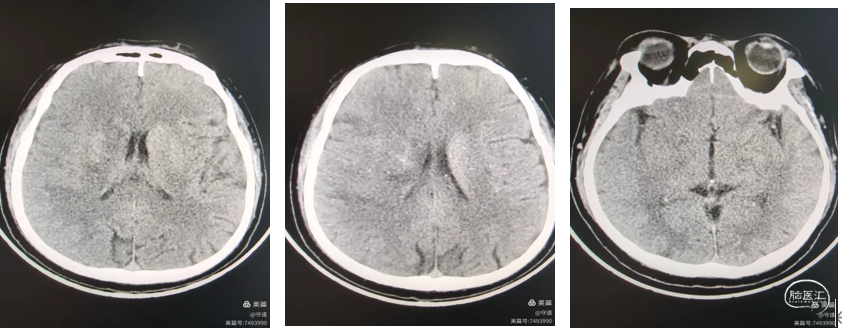

术后2天,复查CT未见明确梗塞和脑水肿征象。患者上下肢力肌力正常,言语正常。患者病情恢复正常。

术后1月再次以言语不利,右侧上下肢力弱再次住院。MRA显示左侧大脑中动脉M1段重度狭窄,急性闭塞并发梗塞风险高。

微导丝携带2.5mm白驹球囊置于M1狭窄部位,在6个大气压下扩张狭窄血管,狭窄较前明显改善。

021灌注微导管置入狭窄以远,输送4.0*23mmEP2支架铆定于狭窄部位,推送支架输送杆,回撤微导管释放支架于狭窄部位。

1.老年患者,ICAS病变,急性血栓闭塞,行SWIM抽拉结合取栓后未Ⅰ期植入支架,服药治疗1月再次出现急性脑血管症状,行球囊扩张、EP2支架植入。